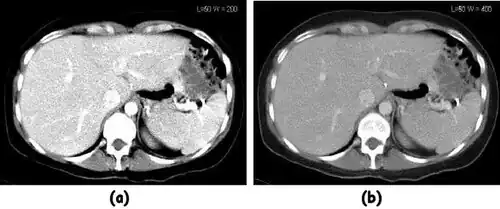

- A choice of filters can generally be selected to enhance either soft tissue features in the image or bone detail. Indeed, the image can be post-processed using a different filter after the scan has been completed if needed. Images can be generated to enhance bone detail or display subtle low contrast masses without the need to re-scan the patient. The filter choice therefore has a major impact on image quality. The two most common filters used in X-ray CT are those due to Ramachandran & Lakshminarayana (commonly called the Ram-Lak) and Shepp & Logan. Viewed in spatial frequency space, the former is essentially a ramp filter with a cut off frequency and the latter combines a smoothing filter with the ramp to attenuate high frequency noise. The ramp filter compensates for the artefacts introduced by the simple back projection process but does not compensate for the increasing noise content of the data with increasing frequency. Images of an axial tomogram reconstructed with a soft tissue and with a bone algorithm can be seen in Figure 7.14.

![]() |

- Examples of image display manipulation are shown in the two figures above. In Figure 7.15.2, the same image of a slice through a patient's liver is displayed using a relatively narrow window (high contrast) and also with a wide window. The image with the narrower window appears noisier, but this is merely a reflection of the fact that the gray scale is spread over a narrow range of CT-numbers.